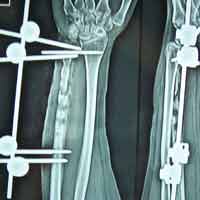

Case:13 Infected nonunion with implant failure

31 years old patient with fracture radius-ulna (1-year-old) with infected non-union was treated with implant removal & external fixation. ‘K’ wiring was done for distal radio-ulna joint stabilization. Bone grafting was done after 3 weeks. Fracture united 6 months’ post-operative.

Pre-Op

Post-op

Imm Post-op

Bone gratfing + ex fix

6 months post-op